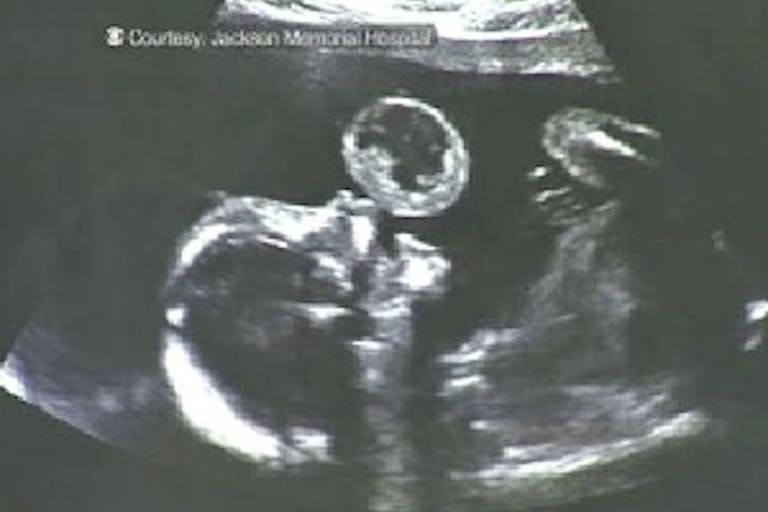

Source: Jackson Memorial Hospital

Recently CBS Miami released an article giving Dr. Quintero the credit for removing a tumor from the mouth of an unborn child. When a tumor the size of a tennis ball was found during an ultrasound of Tammy Gonzalez, the diagnosis was not good. According to CBS Miami, “Doctors told Tammy there was little chance her daughter would survive birth – and if she did, she would require an immediate tracheotomy in order to breath [sic] and have multiple surgeries thereafter.” In the face of this devastating news, Tammy sought the assistance of Dr. Quintero.

Tammy was seventeen weeks pregnant when the surgery was performed. She watched as the doctors skillfully guided their instruments to remove the tumor. According to Tammy, “I could see it floating down. It was like this huge weight had been lifted off. It just floated away and I could see her face.”